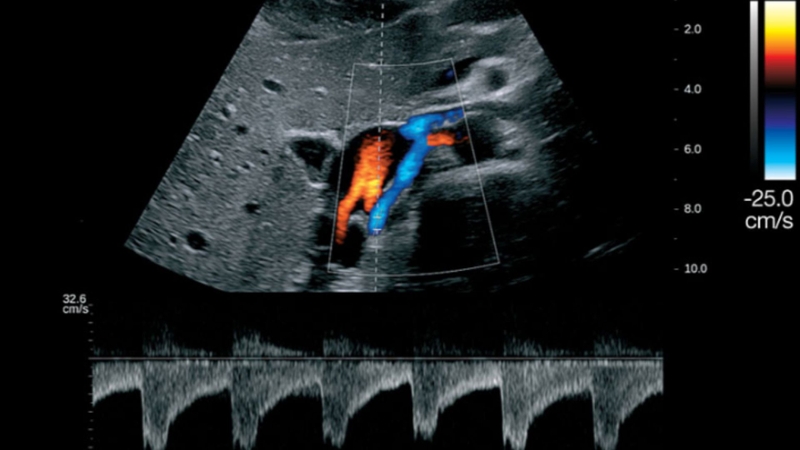

Hiển thị hướng và tốc độ dòng máu bằng màu sắc trên màn hình siêu âm, thường dùng màu đỏ cho dòng máu hướng về đầu dò và màu xanh cho dòng máu hướng xa đầu dò.

Ưu điểm: Giúp đánh giá trực quan dòng máu ở các nhánh mạch nhỏ hoặc phát hiện tổn thương mạch máu như hẹp, tắc hoặc rò động mạch.

Ứng dụng: Rộng rãi trong tim mạch, sản khoa và thần kinh.